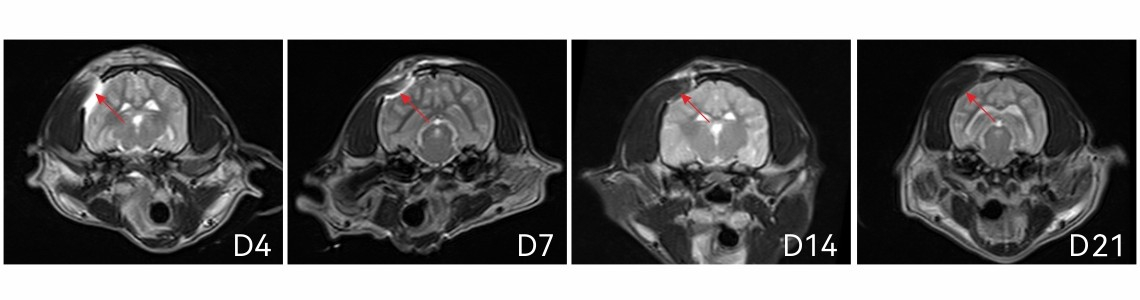

MRI結果顯示:

硬腦膜醫用膠犬顱腦內降解良好,安全無憂;

術后第4、7、14天均可見植入材料。第21天材料基本肉眼不可見。